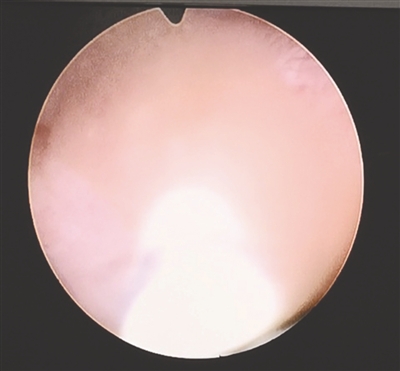

膀胱镜下,能看到涌出的大量泥沙状结石

“她太小了,加上这种肾功能不全的患者,麻醉需要特殊方案,使用不经过肾脏代谢的麻醉药物。”覃道锐介绍说,在于麻醉科制定好具体方案后,使用婴幼儿专用的输尿管支架,经尿道、膀胱、输尿管一路将支架管置入小翁姆的肾盂,就在那一刻,浑浊的脓性尿液裹挟着细碎的结石碎片,像泥沙一样从输尿管中喷涌出来,医生们的心一下子就放松下来。